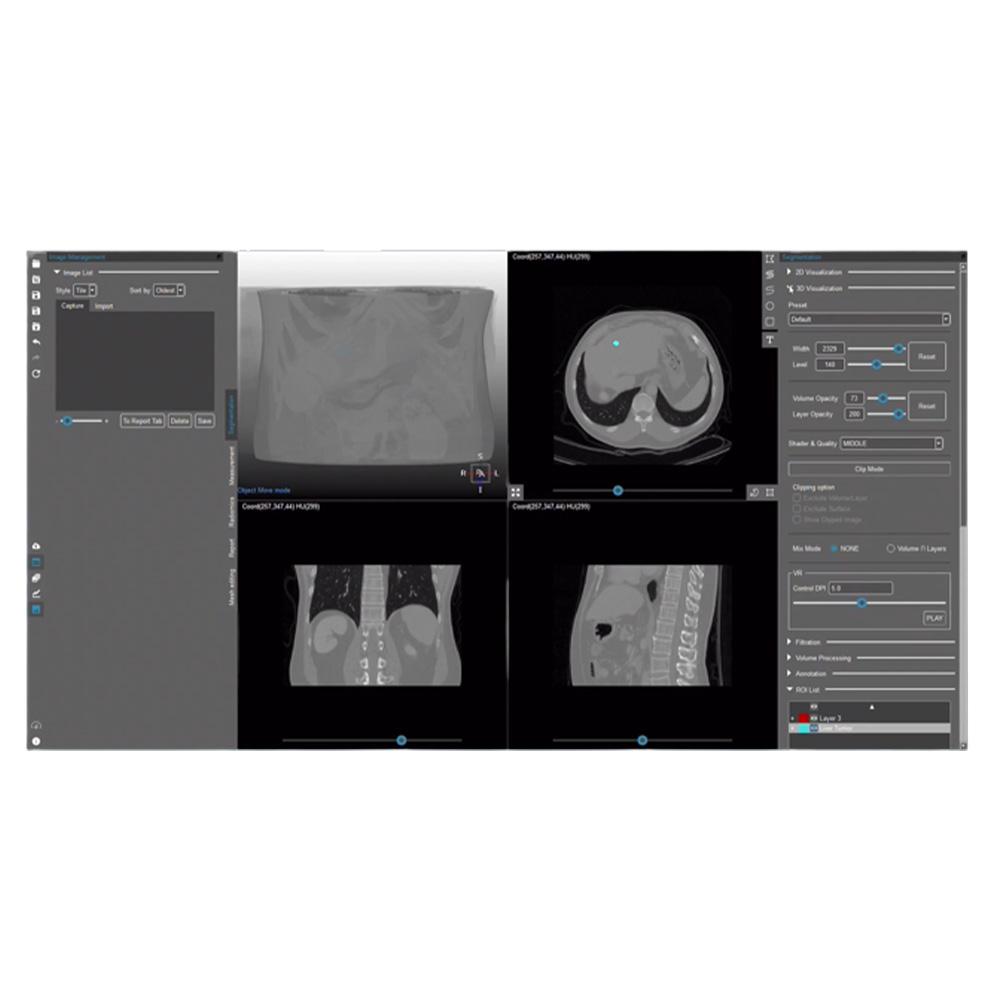

MEDIP PRO is a comprehensive software that processes medical images, enabling image analysis, 3-dimensional construction, modeling, and design with its automatic artificial intelligence (AI) segmentation technology at its core.

MEDIP PRO is equipped with One-Click Segmentation, which helps auto-segmentation

and extracts virtually all human body components in medical images (CT and MR) including patients’ organs and pathologic lesions.

and extracts virtually all human body components in medical images (CT and MR) including patients’ organs and pathologic lesions.

Our technology detects body components including but not limited to lesions from medical images using AI technology and extract quantitative data such as volume and area using our accurate and precise segmentation analysis. This is core technology that sets the basis for the realization of precision medicine by enabling the prediction of the possibility of disease occurrence and monitoring of the patient progress. Based on medical images, we give shape to anatomical digital twin extending our product line to include products for surgical simulation, training, education, as well as patient consultation and diagnosis. Our digital twin expands to the metaverse, a 3D virtual world, enabling medical services and medical education without constraints in time and space.